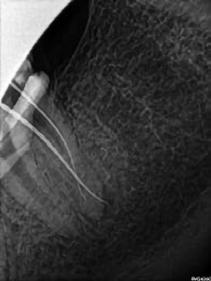

Egy 40 éves hölgy pácienst a jobb alsó második nagyőrlőfogának (47) panaszossága és kopogtatáskor jelentkező érzékenysége miatt irányították dr. Karaś rendelőjébe. A hagyományos technikával készített röntgenfelvételeken a beküldő orvos nem észlelt gyökércsatornák jelenlétére utaló jeleket, ezért úgy gondolta, hogy a fog endodonciai ellátása túlmutat saját kompetenciakörén.

Az első vizsgálat során CBCT-felvétel készült. A felvételen egy kis méretű radiolucens elváltozást észleltünk a mesialis gyökércsúcs körül. Ez alapján azt vélelmeztük, hogy elérhető lehet a mesialis gyökércsatornák átjárhatóságának biztosítása. A disztális gyökér körül nem láttunk gyulladásra utaló jeleket, így a panaszok hátterében valószínűleg a mesialis gyökér végén látható gyulladásos elváltozás állt. További leletként a mesio-bukkális gyökércsatornában (MB) egy törött lentulót is észleltünk (16. a–b ábra).

Az első kezelés célja a törött eszköz eltávolítása és a gyökércsatornák átjárhatóságának biztosítása volt. Helyi érzéstelenítés és a kofferdám felhelyezését követően a meglévő tömés eltávolításra került. Ezt követően láthatóvá vált, hogy mindhárom gyökércsatorna-bemeneti nyílást Endomethasone N fedi. Ezt az anyagot ultrahangos fej (U-file) és 5,25%os NaOCl alkalmazása révén távolítottuk el. Ezután a lentuló is láthatóvá vált. Sajnálatos módon a lentuló nem cementbe volt ágyazva, hanem a gyökércsatorna görbülete mögött egy fel nem tágított gyökércsatornafal-szakaszba ékelődött be. A tört részt kalcifikálódott szövetek borították. Ez alapján azt vélelmezzük, hogy az első kezelés során ezt a gyökércsatorna-szakaszt még élő fogbél töltötte ki. Ekkor azt a döntést hoztuk, hogy a kalcifikálódott szöveteket 10-15 percen keresztül végzett lézerrel aktivált folyamatos 5,25% NaOCl átöblítéssel megpróbáljuk eltávolítani. A terv sikeres volt, a

betört eszköz és a kalcifikálódott szövetek is eltávolításra kerültek. A betört műszer egészben történő eltávolításáról kontrollröntgen segítségével győződtünk meg (17. ábra)

A páciens öklendezése miatt a beavatkozások nehezen voltak elvégezhetőek. A kontrollröntgen elkészítése után a csatornát AutoSWEEPS módban alkalmazott SkyPulse lézerrel aktivált 17%-os EDTA és 5,25% NaOCl oldattal átöblítettük. A lézert néhány 15-20 másodperces ciklus idejére alkalmaztuk, majd a csatorna átjárhatóságát kézi tű segítségével ellenőriztük. Ekkor egy újabb kontrollröntgen készült, amely azt mutatta, hogy a tűnkkel az előzőleg elkészített gyökértömés végénél mélyebbre jutottunk (18. ábra). Ezután a fogat egy kompozitból készült ideiglenes töméssel zártuk, majd visszarendeltük egy következő időpontra.